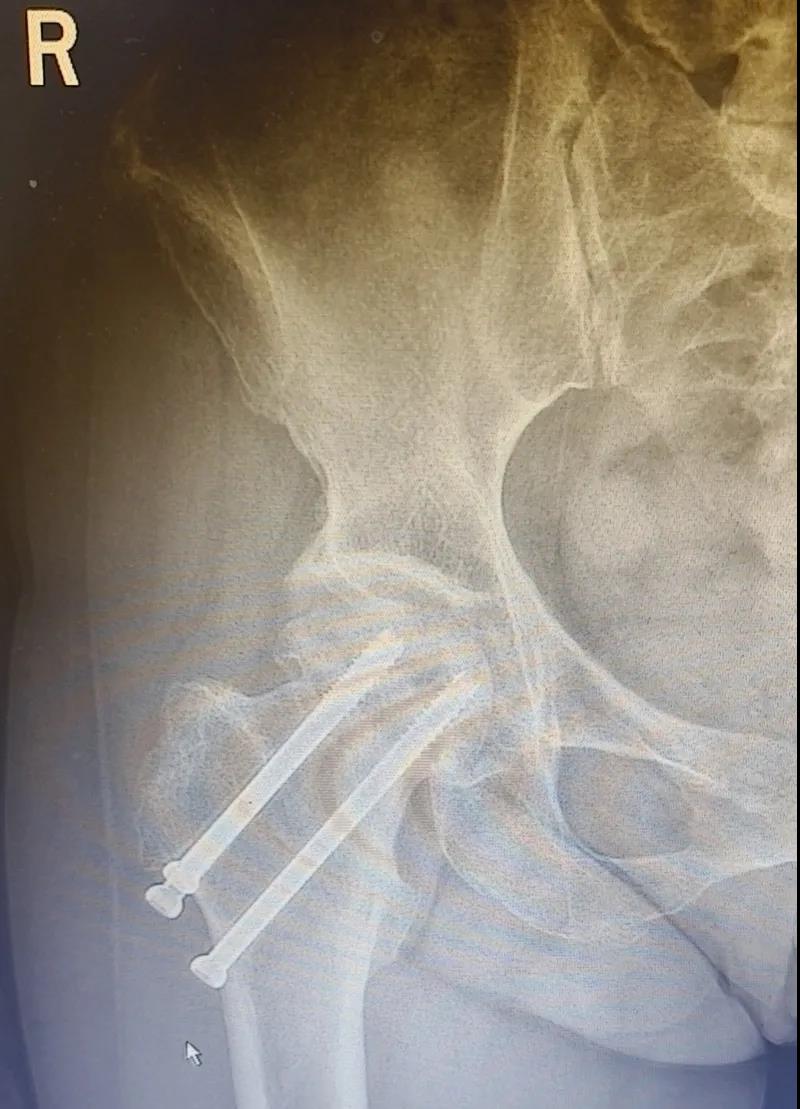

據李女士自述,自己于3年前因外傷致右股骨頸骨折,當時在其他醫院做了右股骨頸骨折閉合復位螺釘內固定術,一年后右髖出現疼痛并逐漸加重,且休息不能緩解,行走時就像有座山壓身上一樣。

(△術前影像,右股骨頸骨折內固定術后股骨頭壞死)